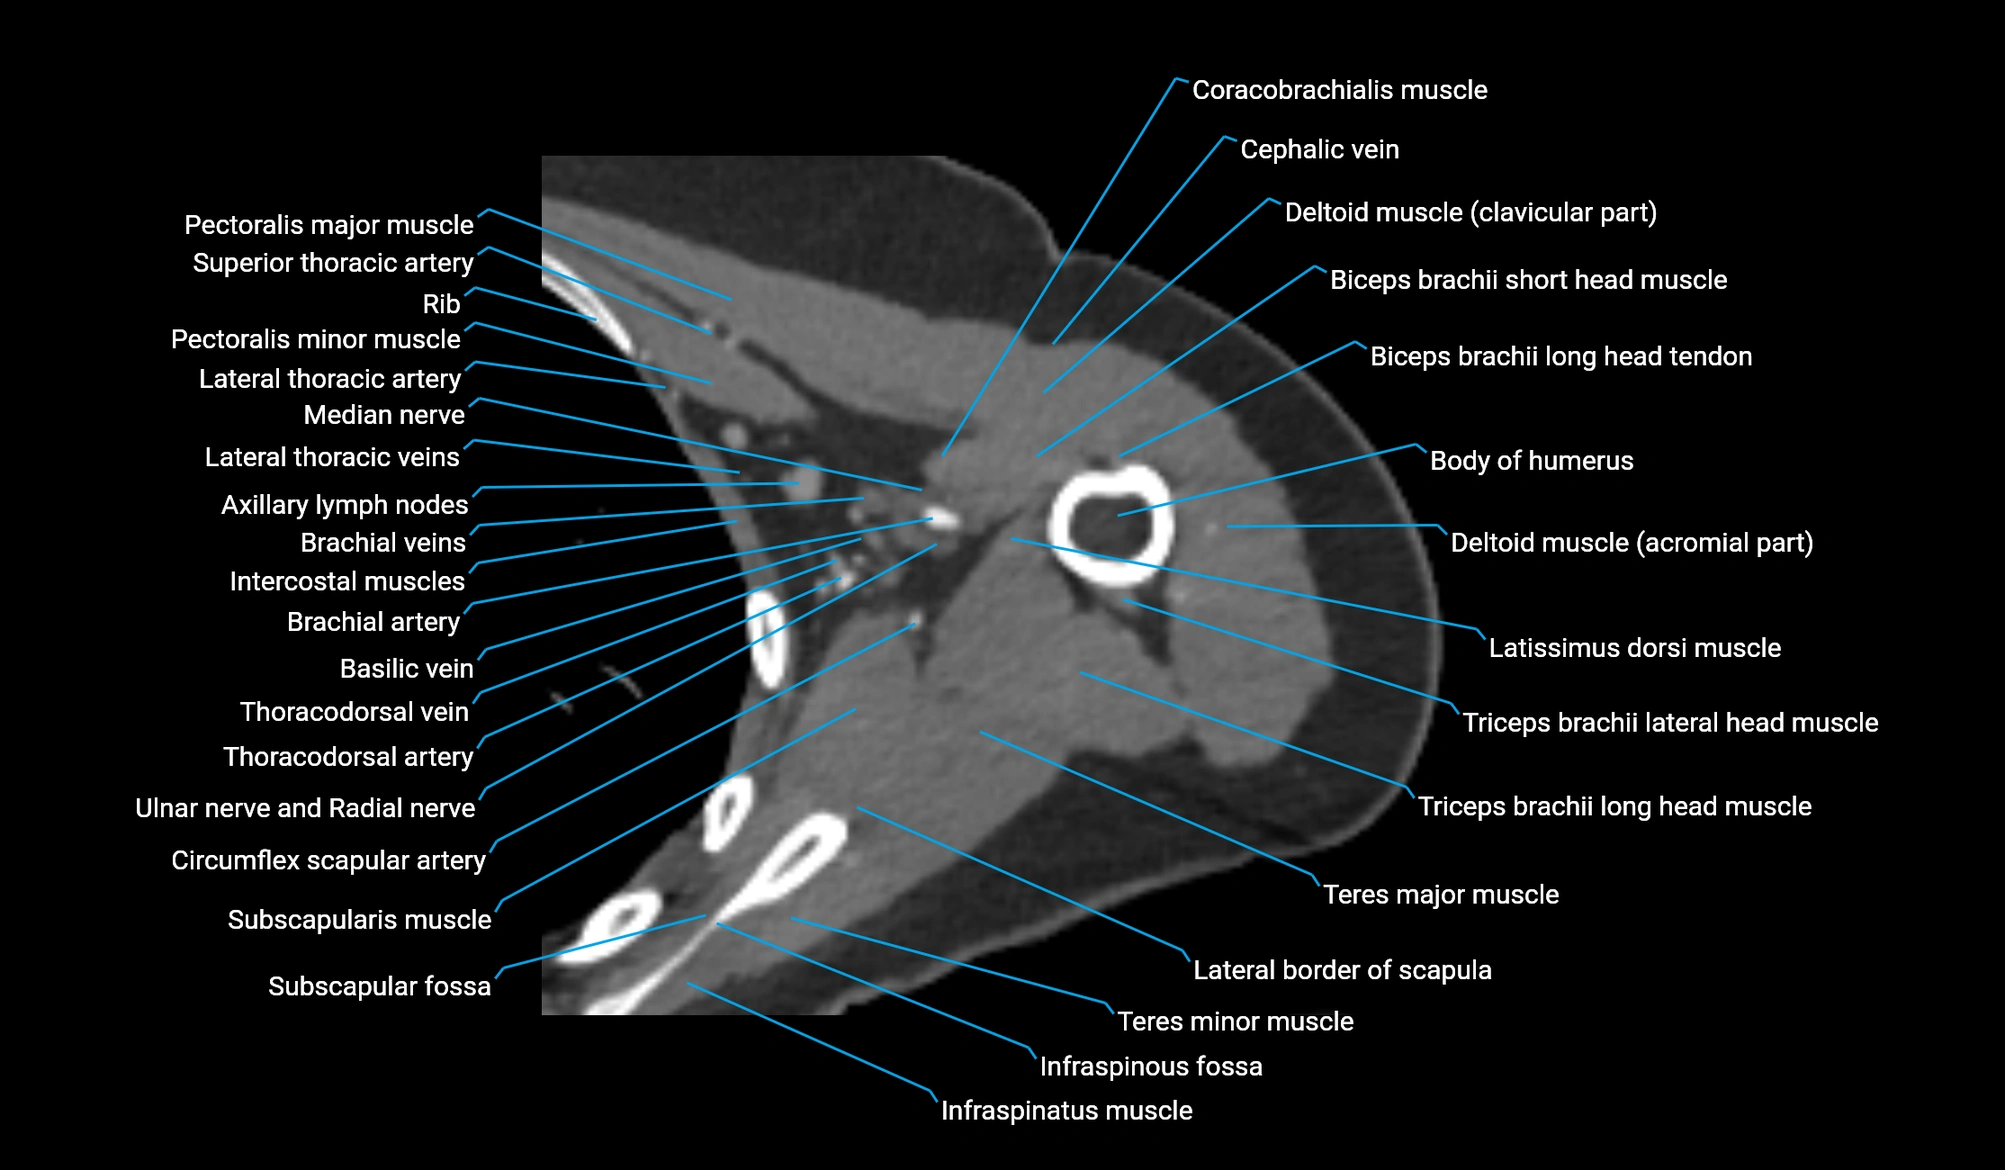

- Acromial part of deltoid muscle

- Axillary lymph nodes

- Basilic vein

- Brachial artery

- Brachial fascia

- Brachialis muscle

- Cephalic vein

- Clavicular part of deltoid muscle

- Coracobrachialis muscle

- Deep brachial artery

- Infraspinatus muscle

- Infraspinous fossa

- Lateral border of scapula

- Lateral head of triceps brachii muscle

- Long head of triceps brachii muscle

- Median nerve

- Pectoralis major muscle

- Pectoralis minor muscle

- Subscapular fossa

- Subscapularis muscle

- Supraspinatus muscle

- Teres major muscle

- Teres minor muscle

- Thoracodorsal artery